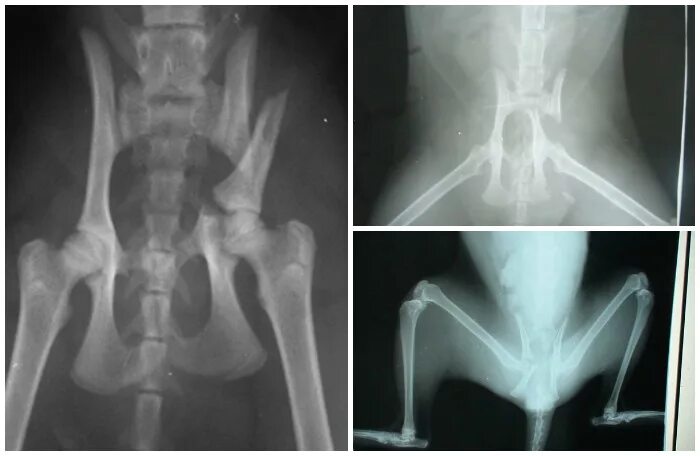

Срослась п и ж